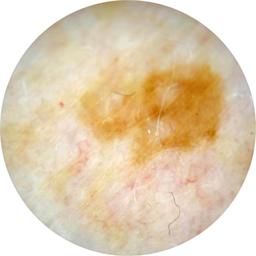

ISIC_7268078

Information

1781 x 1781

Clinical

Field Value

acquisition_day 226

age_approx 60

anatom_site_1 Trunk

anatom_site_2 Posterior trunk

anatom_site_general posterior torso

concomitant_biopsy False

diagnosis_1 Benign

diagnosis_confirm_type single image expert consensus

family_hx_mm False

image_manipulation instrument only

image_type dermoscopic

lesion_id IL_3039460

patient_id IP_4030734

personal_hx_mm True

sex female